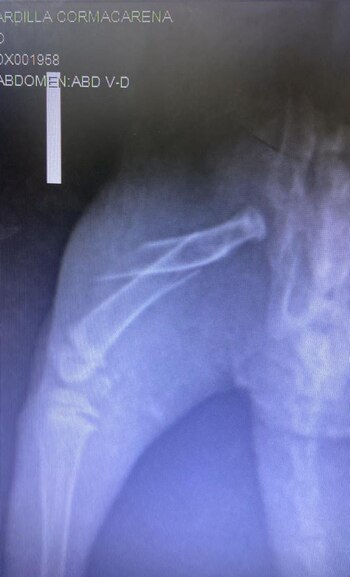

Luego de una valoración médica y de examinar la gravedad de sus heridas, el animal silvestre fue llevado hasta la clínica veterinaria ‘Solo Patas’, ubicada en la zona de Vanguardia en Villavicencio. Allí se le realizaron una serie de radiografías para luego ser intervenida quirúrgicamente, implantando en su extremidad una placa de platino, material utilizado para estabilizar sus huesos y restaurar sus fracturas.

Luego de unas horas en el quirófano, la cirugía fue todo un éxito y el animal respondió satisfactoriamente, recuperando la movilidad en su extremidad y volviendo a caminar al siguiente día, tras aplicarle algunos medicamentos para el dolor, sutura para cicatrizar, anestesia y antibiótico.